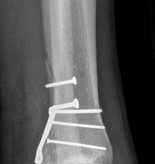

Definitive Lag Screw and Plate Fixation

The definitive fixation sequence is critical to achieving absolute stability:

1. Independent Lag Screws: If the fracture morphology permits, independent lag screws are placed perpendicular to the fracture plane. The standard sequence is utilized: 4.5mm gliding hole in the near cortex, insertion of the drill sleeve, 3.2mm thread hole in the far cortex, countersinking, measuring, tapping, and screw insertion.

2. Plate Application: A pre-contoured anatomic locking plate or a standard buttress plate (e.g., L-buttress or T-plate) is applied to the lateral cortex. The plate must sit flush against the bone at the apex of the fracture.

3. Diaphyseal Fixation First: To achieve the buttress effect, the plate is first secured to the intact distal diaphyseal segment using cortical screws. If the plate is slightly under-contoured, tightening these diaphyseal screws will drive the proximal portion of the plate into the metaphyseal flare, compressing the articular fragment.

4. Periarticular Screws: Subchondral "rafting" screws are then inserted through the proximal holes of the plate. These screws support the elevated articular cartilage and neutralize any remaining forces. In modern osteosynthesis, locking screws are frequently utilized in the periarticular segment to create a fixed-angle construct, which is particularly beneficial in osteopenic bone.

Image

Fluoroscopic Verification

Before closure, comprehensive fluoroscopic imaging is mandatory. True AP and lateral views, along with oblique projections, are obtained to confirm anatomic reduction of the joint line, verify restoration of mechanical alignment, and ensure that no hardware has penetrated the intra-articular space.